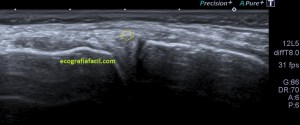

En este breve post te voy a presentar unas imágenes muy bonitas de una vesícula, en una paciente que acude a la cita de ecografía por sospecha de patología a ese nivel, con molestias anodinas e inespecíficas en el contexto de un estudio de su especialista de digestivo.

Observa las imágenes y luego te explico los hallazgos:

Cuando hice el corte longitudinal de la vesícula pude ver hasta tres patologías distintas, una adeomiomatosis (sin artefacto en cola de cometa), una litiasis vesicular y barro biliar, 2,3 y 4 respectivamente.

La adenomiomatosis, como un aumento de la ecogenicidad y el tamaño de la pared vesicular, la litiasis como una estructura hiperecogénica con sombra acústica posterior y el barro biliar, hiperecogénico rellenando toda la estructura ovoidea de la vesícula.

El cuello vesicular estaría afectado por la adenomiomatosis, el cuerpo por la litiasis y el barro ocuparía el fundas vesicular.

Para el estudio de la adenomiomatosis es obligado que el foco esté situado en la línea de interés, eso hará que las imágenes sean más nítidas y podamos estudiar dicha ecoarquitectura y su patología convenientemente.